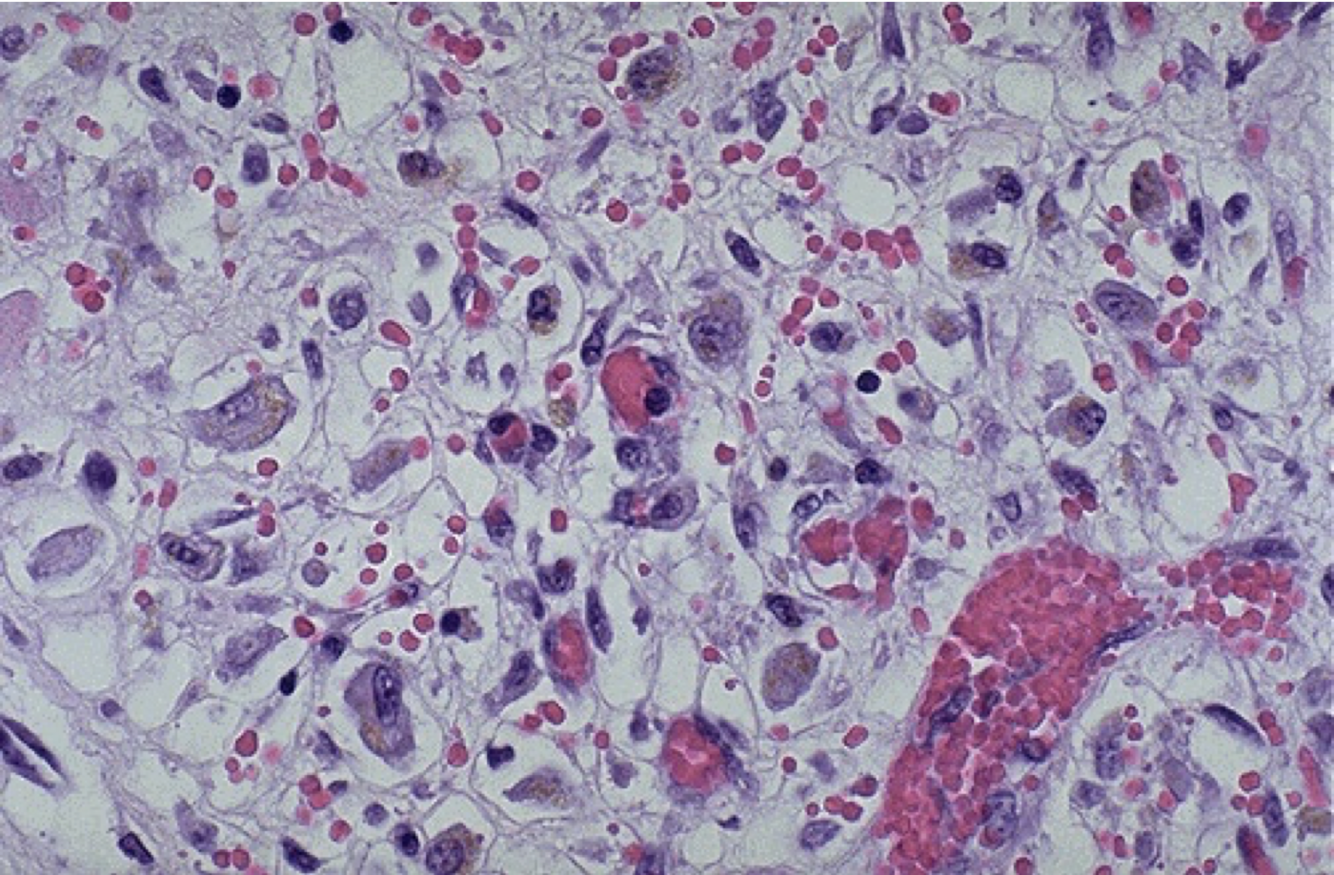

What is suppuration?

The formation of pus:

What is suppuration usually due to?

A bacterium (pyogenic bacteria)

What can suppuration form?

An abscess - a collection of pus in the body eg. in an organ, soft tissue, skin